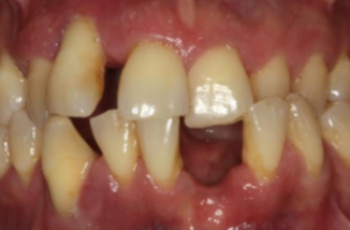

Absceso periodontal Nueva Clasificación Workshop 2017 | UCM Absceso periodontal Casos Clínicos E.T.E.P. – Nueva Clasificación Este proyecto de Casos Clínicos... Periodontitis, estadio IV, grado C Nueva Clasificación Workshop 2017 | UCM Periodontitis, estadio IV, grado C Casos Clínicos E.T.E.P. – Nueva Clasificación Este proyecto de Casos Clínicos... Periodontitis, estadio II, grado A Nueva Clasificación Workshop 2017 | UCM Periodontitis, estadio II, grado A Cátedra Extraordinaria DENTAID en Investigación Periodontal La Cátedra Extraordinaria... Tratamiento de un diente uniradicular afectado por una lesión... Tto. Periodontal | USC Tratamiento de un diente uniradicular afectado por una lesión... Con frecuencia nos encontramos ante la cuestión de tratar de conservar un diente con pronóstico cuestionable o... Tratamiento de un paciente con periimplantitis Tto. Periimplantario | UCM Tratamiento de un paciente con periimplantitis Presentamos un caso clínico sobre el tratamiento de un paciente con periimplantitis, elaborado... Tratamiento de un paciente con periodontitis crónica I Tto. Periodontal | UCM Tratamiento de un paciente con periodontitis crónica I Presentamos un caso clínico, elaborado por los Doctores Eduardo Montero y David Herrera de la... Efectividad del Tratamiento en Periodontitis Agresiva Tto. Periodontal | UIC Efectividad del Tratamiento en Periodontitis Agresiva El mantenimiento de la dentición natural en estado de salud ha sido un objetivo importante en... Lesión endo-periodontal combinada verdadera en raíz mesiovestibular de... Tto. Periodontal | USC Lesión endo-periodontal combinada verdadera en raíz mesiovestibular de... Presentamos un caso clínico sobre un paciente que acude a la clínica dental por molestias generalizadas.... Tratamiento multidisciplinar de un paciente con Periodontitis avanzada... Tto. Periodontal | USC Tratamiento multidisciplinar de un paciente con Periodontitis avanzada... Las enfermedades periodontales tienen una elevada prevalencia en la población adulta en España....